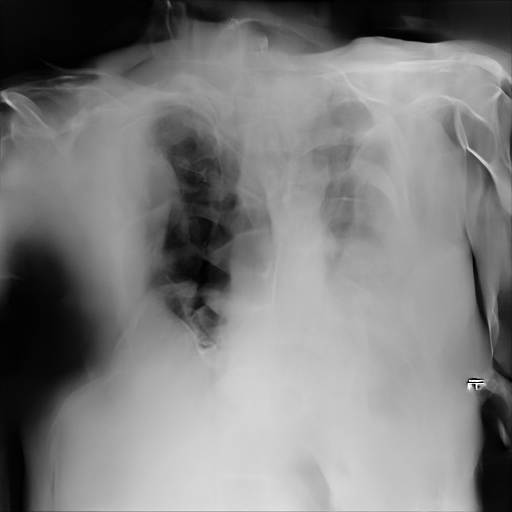

Refer to caption

(a) Original,

case 1 with a block.

(b) ϵ=102HWitalic-ϵsuperscript102𝐻𝑊\epsilon=10^{2}\cdot H\cdot W,

case 1.

(c) Original,

case 2 with a block.

(d) ϵ=102HWitalic-ϵsuperscript102𝐻𝑊\epsilon=10^{2}\cdot H\cdot W,

case 2.

Figure 4: Block obfuscation with DP-GLOW.

Here, we assume two possible privacy leakage scenarios. To CXR images, we intentionally add features that can lead to the re-identification of the subject appearing in a CXR image. The first feature is an artificial block marker. The second feature is a rare anatomical abnormality known as situs inversus simulated by flipping a CXR image along the vertical axis. Figs. 3(a) and 3(c) show CXR images with the artificial block marker. Fig. 5(a) shows a flipped CXR image to represent a case of situs inversus. We applied DP-GLOW to these CXR images. In Figs. 3(b) and 3(d), the image domain LDP fails to obfuscate the artificial block marker with a moderate privacy budget. In contrast, in Figs. 4(b) and 4(d), DP-GLOW successfully obfuscated the artificial block marker with the moderate privacy budget. On the other hand, the anatomical shape of the chest and the abnormal opacity (hilar regions in the case 1) are preserved. In Fig. 5(b), we observed that the right edge of the heart does not become obfuscated with the image domain LDP. In contrast, in Fig. 6(b), we observed that the right edge of the heart becomes obfuscated and the heart appears at the center of the thoracic cage with DP-GLOW. However, DP-GLOW with this privacy budget is insufficient to almost completely erase the feature of situs inversus.